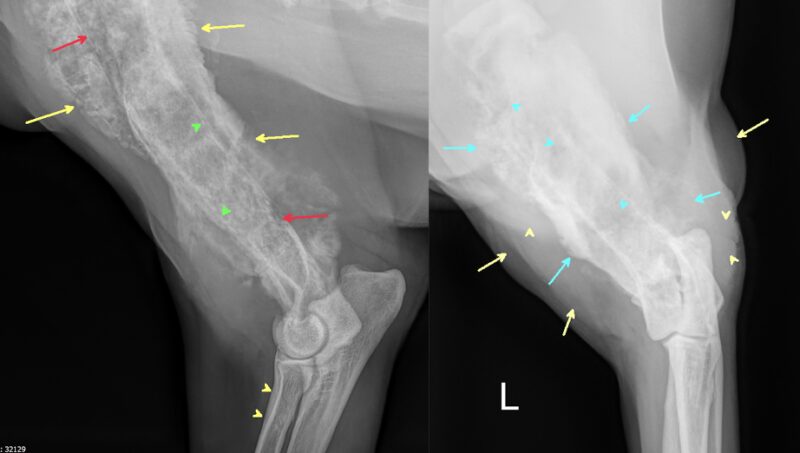

Vielen Dank für die Zusendung der Röntgenbilder. Ein wirklich eindrucksvoller Fall! Es liegen zwei Röntgenaufnahmen des linken Humerus, inkl. Ellbogengelenk, im medio-lateralen, sowie kaudo-kranialem Strahlengang vor. Begleitend besteht eine Röntgenaufnahme des Thorax in dextro-sinistralem Strahlengang (Abb. 1, Abb. 2). Im Röntgenbild der linken Vordergliedmaße zeigt sich im Bereich der gesamten Diaphyse des Humerus, bis in die angrenzenden metaphysären Abschnitte reichend, eine hochgradige, unregelmäßige osteoproliferative Reaktion (blaue Pfeile Abb. 3). Diese periostale Reaktion weist eine heterogene Röntgendichte auf. An ihrer ausgeprägtesten Stelle übersteigt die Proliferation den Durchmesser des normalen Humerus deutlich. Besonders an der kaudalen Humeruskontur besteht hochgradige, laminar geschichtete Knochenneubildung (gelbe Pfeile, Bild links).

Die Markhöhle (Medulla) erscheint hochgradig heterogen (blaue Pfeilköpfe). Entlang des Endosteums sind multifokale Irregularitäten (grüne Pfeilköpfe), sowie multifokale kortikale Lysen (rote Pfeile) sichtbar, die den Befund einer destruktiv-proliferativen Knochenerkrankung verdeutlicht. Eine pathologische Fraktur ist in den vorliegenden Aufnahmen nicht erkennbar.

Das umgebende Weichteilgewebe zeigt eine deutliche Umfangsvermehrung (hellgelbe Pfeile und Pfeilköpfe, Bild rechts). Zudem findet sich am proximalen Radius eine geringgradige, glattrandige periostale Reaktion (gelbe Pfeilköpfe, Bild links).